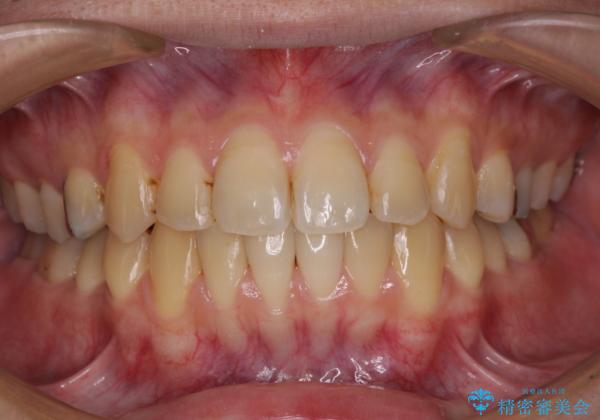

前歯のクロスバイトをインビザラインで矯正治療

- 前歯のデコボコとクロスバイトを気にして来院された患者様です。

前歯を早く整えたいとの希望があったので、ワイヤー矯正にて短期間でクロスバイトを解消し、その後インビザラインにて整えることとしました。